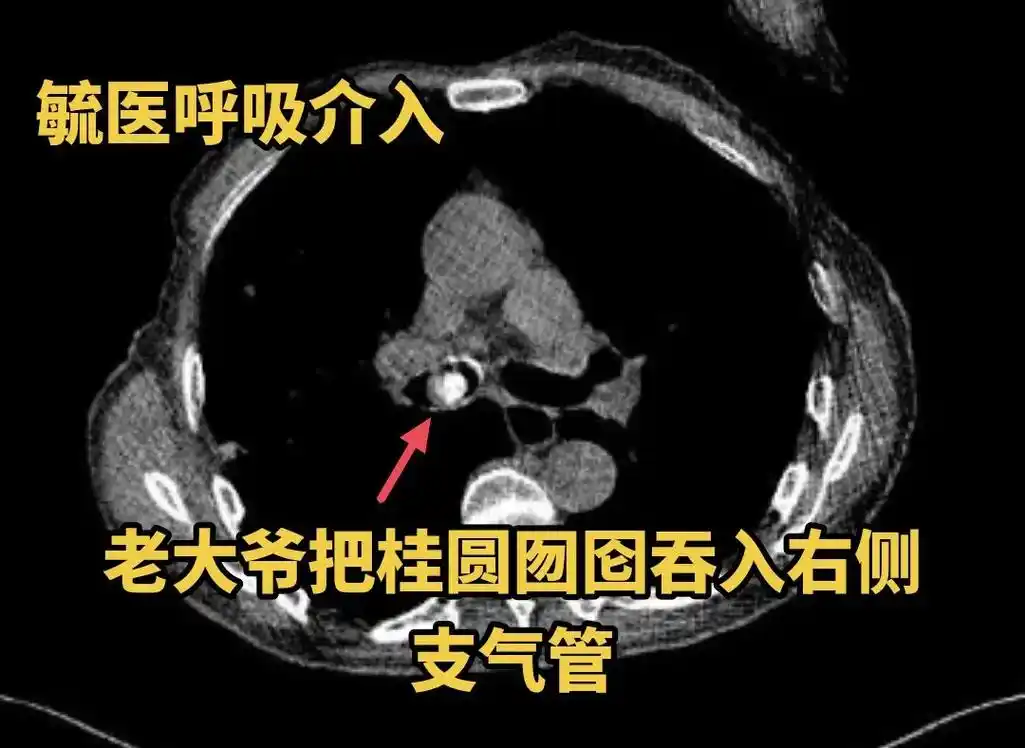

江湖救急之异物取出.